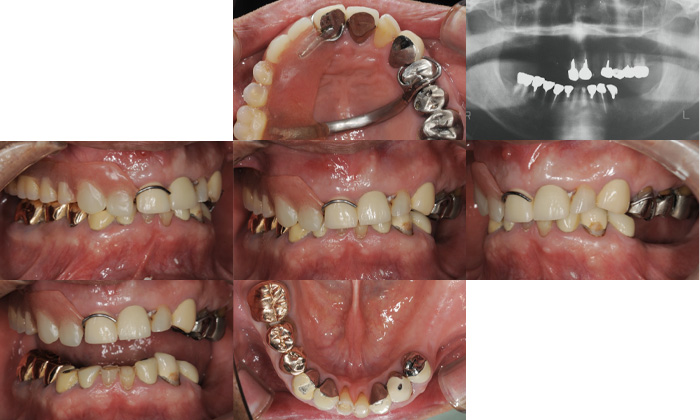

大阪市阿倍野区の歯医者「脇歯科医院」では、患者さまからお悩みやご要望をしっかり伺い、口腔内の状態をしっかり把握した上で、最善のご提案をしています。こちらでは、「孫と食事を楽しみたい」と願う患者さまの治療ケースをご紹介します。

孫ができて、一緒におやつや食事を楽しみたいと思っているものの、歯が悪いため孫と同じ物が食べられないと悩まれていました。一緒にハワイ旅行に行った際にも、ハンバーガーを丸かじりできず、辛い思いをされたそうです。

患者さまは若い頃、お仕事が忙しかったこともあり、痛くなった時だけ歯医者に行って、その場しのぎの治療をされていたそうです。そのため、歯が悪くなる根本を改善できず、再発を繰り返してしまい、お口全体がボロボロになっていました。

お口全体を見据えた上で治療計画を立て、お身体の負担を考えて治療を進めることに。これまでの治療で入れ歯を入れていたところもあれば、入れ歯をせず歯が抜けている部分や、すり減っている歯もありました。

「しっかり噛める」ことがゴールであるため、まずは歯がないところに天然歯のような噛み心地を再現できるインプラントを入れました。上部構造には再発を防ぎ、良い状態を長く保てる機能性に優れたセラミックの歯を入れています。

もちろん、ただインプラントやセラミック治療をすれば良いわけではありません。「しっかり噛める」という患者さまの願いを叶えるには、噛み合わせも重視すべきです。そのため、お口全体を診ながら、バランスを考えて噛み合わせを整え、お口全体の咬合再構成も行いました。